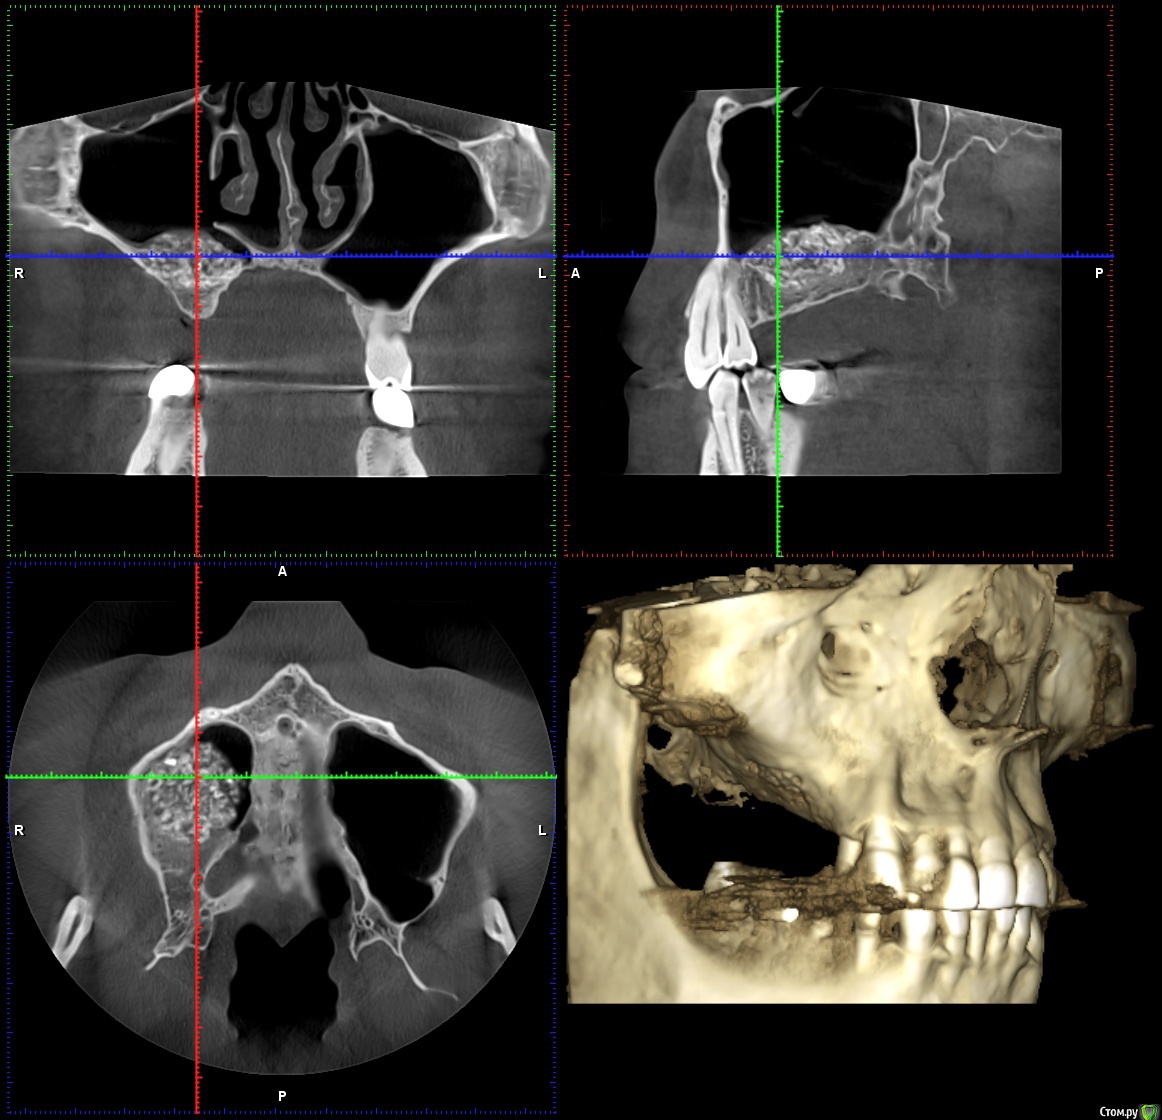

Reyb Опубликовано 14 марта, 2018 Поделиться Опубликовано 14 марта, 2018 Здравствуйте уважаемые доктора.У меня такая проблема,в декабре 2016 года мне делали открытый синус лифтинг справа.Через день-два после операции у меня начались боли,что я воспринял как норму.Дней через 9 врач снял швы,осмотрел и сказал,что всё в норме и боли должны скоро пройти.Через месяц,когда стало можно сморкаться,сразу заметил что справа высмаркивается слизь с кровью,да и к тому же боль не проходила.Пошёл к своему врачу.Он осмотрел и сказал,что всё в приделах нормы (по панорамному снимку).Спустя 1,5 месяца,при сморкании стал замечать ещё и гной с кровью.Спустя ещё где-то 2-3 недели периодически стало закладывать нос.Когда подошло время ставить импланты врач посмотрев КТ сказал,что нельзя,так-как гайморит справа и направил к лору.Пролечившись у лора,стал сомневаться в продолжении имплантации.Спустя 15 месяцев ноющая боль на стороне операции осталась и при сморкании иногда что-нибудь да вылетит из правой ноздри (сгустки крови или почти сухая корка в слизи).На сегодняшний день как и с первых дней после синус лифтинга самочувствие как-будто приболел,писк в ушах(появлялся всегда когда чем-нибудь болею).На КТ просматривается неоднородность и затемнения в материале.Что это,отторжение,инфицирование или норма?К своему стоматологу претензий не имею так-как сделано было на мой взгляд на высоком уровне.Что посоветуете делать в моём случае? КЛКТ от 1.03.2018г.http://my-files.ru/qki4xs Ссылка на комментарий

wladdX Опубликовано 15 марта, 2018 Поделиться Опубликовано 15 марта, 2018 Несколько скринов Ссылка на комментарий

Irouil Опубликовано 15 марта, 2018 Поделиться Опубликовано 15 марта, 2018 Когда КТ делали? У Вас открыт нижний носовой ход в пазуху, уже это одно может вызывать выделения из ноздри, на которые Вы жалуетесь. Да и болевые ощущения, в принципе. Кажется графт не звонил, слизистая спокойная вокруг него, но может быть и не пророс новой костью. Надо готовиться под имплантацию, я считаю, если при сверлении обнаруживается несостоятельность графта - удаление его из пазухи и реоперация через месяц Ссылка на комментарий

Reyb Опубликовано 15 марта, 2018 Автор Поделиться Опубликовано 15 марта, 2018 Когда КТ делали? У Вас открыт нижний носовой ход в пазуху, уже это одно может вызывать выделения из ноздри, на которые Вы жалуетесь. Да и болевые ощущения, в принципе. Кажется графт не звонил, слизистая спокойная вокруг него, но может быть и не пророс новой костью. Надо готовиться под имплантацию, я считаю, если при сверлении обнаруживается несостоятельность графта - удаление его из пазухи и реоперация через месяц Когда КТ делали? У Вас открыт нижний носовой ход в пазуху, уже это одно может вызывать выделения из ноздри, на которые Вы жалуетесь. Да и болевые ощущения, в принципе. Кажется графт не звонил, слизистая спокойная вокруг него, но может быть и не пророс новой костью. Надо готовиться под имплантацию, я считаю, если при сверлении обнаруживается несостоятельность графта - удаление его из пазухи и реоперация через месяцКТ делал 1 марта 2018г. До синуслифтинга выделений не было.Такого чтоб самопроизвольно из носа текло,нет.Только при сморкании бывает,что вылетит не большой сгусток крови. Ссылка на комментарий